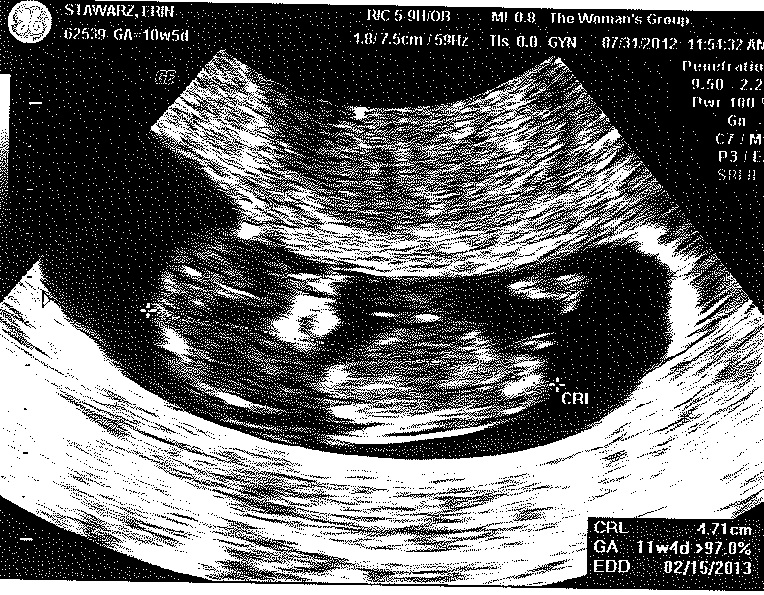

Baby S – 10 weeks